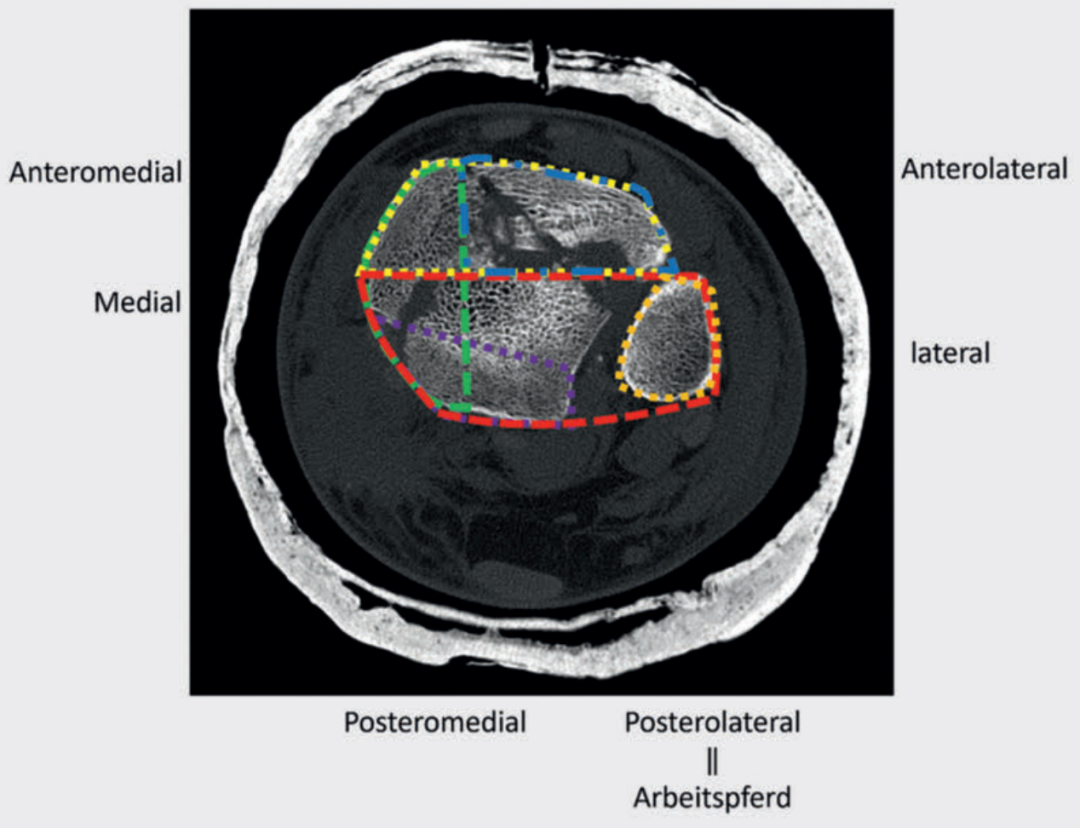

如今,在Pilon骨折的手术治疗中,常规补充进行CT检查已成为标准流程。通过三维重建(容积重建,VRT)技术,能够更清晰地了解骨折的复杂性与形态特征。研究表明,借助三维重建图像进行AO/OTA分型,观察者间的一致性良好;与二维重建图像相比,三维重建图像在手术入路规划和预期接骨板放置位置判断方面的准确性显著更高。

手术入路的选择需综合考虑软组织损伤情况、骨折形态,并结合 “四柱概念” 和 “骨折图谱概念”。在术前规划中,分析主要骨折线和次要骨折线至关重要。约90%的骨折可通过后外侧入路联合前方入路进行治疗。若因骨折形态特殊,需对骨折进行 360° 全方位固定,可将患者置于侧卧位,通过该体位可联合采用后外侧入路和扩大入路。

病例1在受伤后送往医院急诊,首先进行了跨踝关节外固定架。尽管患者初始存在Ⅱ度闭合性软组织损伤,但由于及时进行了复位并植入外固定架,未需实施筋膜间室切开术。在术前CT图像中,可清晰观察到3个主要骨折块及1个中央粉碎区。通过及时植入外固定架,可恢复关节位置,并有效避免软组织损伤进一步加重。